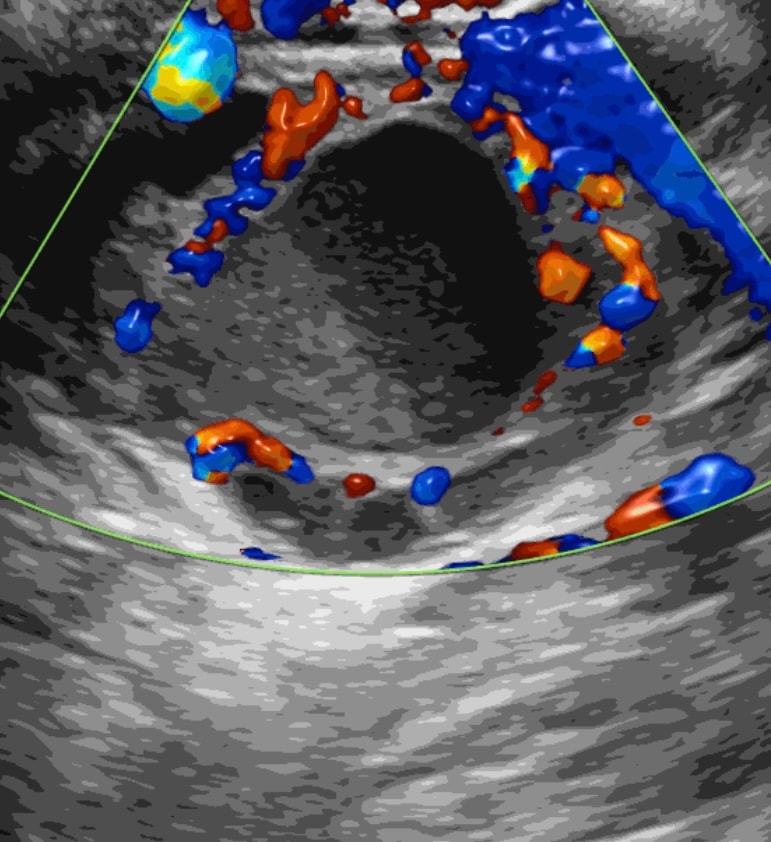

"На УЗИ-снимке врач описывает два жидкостных образования: 7 мм и 25 мм. Образования с мелкодисперсной взвесью - это как раз эндометриоидные кисты. Тот гиперэхогенный компонент, который Вы выделили на снимке, это пристеночное гиперэхогенное аваскулярное образование в составе эндометриоидной кисты. Такие образования бывают очень часто, это не дермоидная киста.

Это структура эндометриоидной кисты, это киста с высокой степенью воспалительной активности, так как там пристеночно образуется фиброзный компонент. Это говорит о том, что даже если Вы не лечите эту кисту, все равно овариальный резерв со временем снижается на фоне выраженного воспаления. Не рекомендуется сейчас удалять кисту даже при высоком овариальном резевре. Во-первых, потому что он сильно снижается в 95% случаев при образованиях такого вида и такого размера. Во-вторых, сама операция способствует распространению эндометриоза, двустороннему поражению, т.е. может перейти на другой яичник. Также в период планирования беременности есть риск рецидива. На практике мы часто сталкиваемся с такими проблемами.